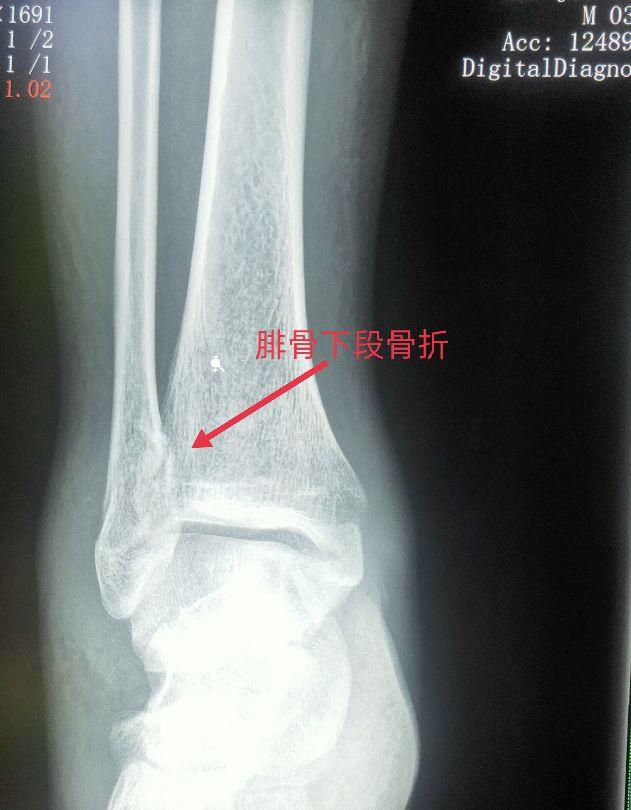

四、踝关节部位的骨折、脱位X线片

车祸、摔跤、跌倒都会造成骨折或脱位。以踝部、距骨、跟骨多见。

脚踝是哪个部位图解,脚踝是哪个部位图解视频(学习《X线读片指南》骨、关节系统——踝关节)